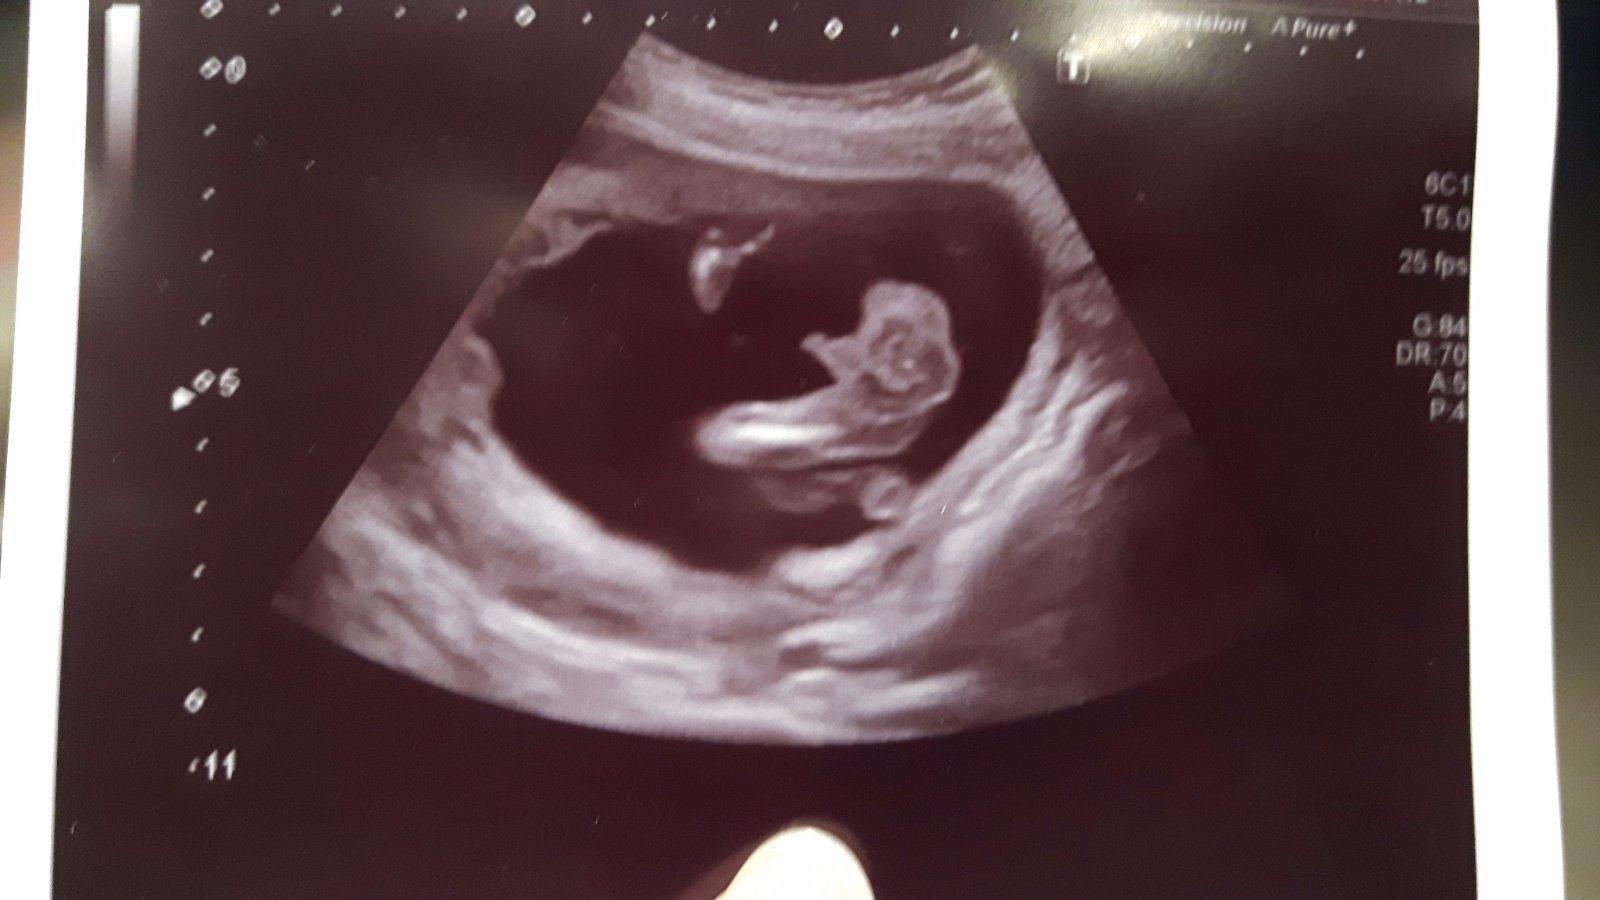

Ahoj holky, krásný nový rok! 👍 Já byla dneska na kontrole a pinďa se neukázal, tak máme zatím potvrzeno jen z prvotrimestrálního screeningu, uvidím co za měsíc, ale asi už mu neupadne 👶😅

Tohle 26.tyden, ale krasne to bylo vidět už ve 20.tem 🙂